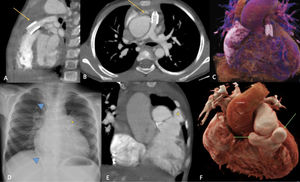

Pre- and post-operative images of a case of Tetralogy of Fallot underwent RVOT stenting followed by intracardiac repair. Preoperative cardiac CT (A–C) showing RVOT stent in situ (arrows in A and B) with good flow in main and branch pulmonary arteries. Chest radiograph (D) two years after intracardiac repair showing prominent mediastinal bulge in the location of RVOT (asterisk) with vascular plugs in the aortopulmonary collaterals (arrowheads). Coronal reconstructed image (E) of cardiac CT showing pseudoaneurysms of the RVOT patch (asterisk). The reconstructed CT cinematic rendering images better depict the two mirror-image proximal suture line aneurysms (arrows in F). CT: computed tomography; RVOT: right ventricular outflow tract.

Right ventricular overflow tract aneurysms are extremely unusual following transannular patches unlike conduit repairs, with an incidence of 0.28%.1 Residual outflow tract obstruction, pulmonary regurgitation, trauma, ventriculotomy, type of suture material, continuous running sutures, partial thickness sutures and postoperative infection are contributing factors for dehiscence of the reconstructed RVOT, hematoma formation and wall thinning.2 Our case is a rare description of multiple proximal suture line RVOT aneurysms after transannular patch repair in a stented RVOT. Factors that may have contributed to the development of an aneurysm include: ventriculotomy incision, residual branch pulmonary artery stenosis leading to RV hypertension, and free pulmonary regurgitation. Surgical aneurysm repair is advised to prevent complications related to mediastinal compression, infection, thrombosis, and rupture (Figure 1).